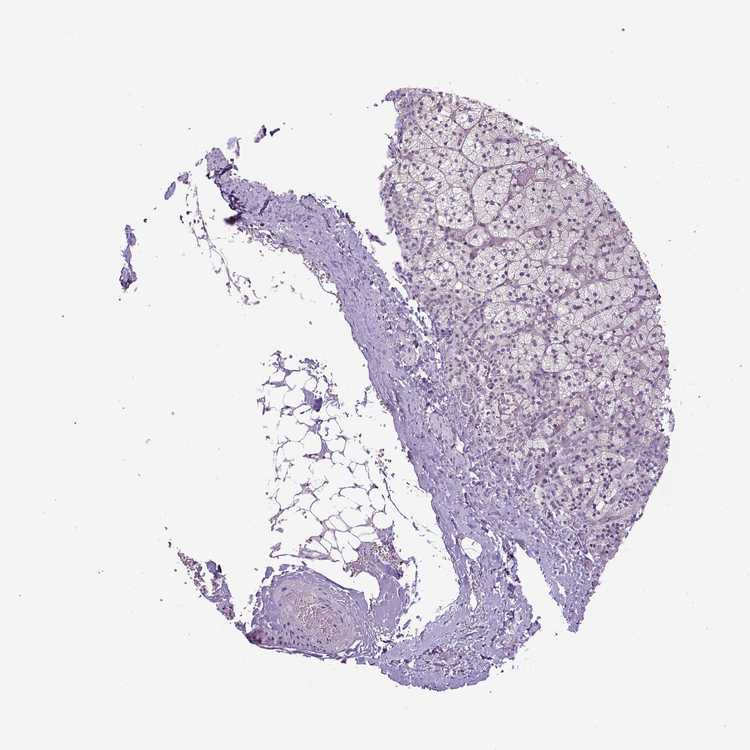

TISSUE PRIMARY DATA ADRENAL GLAND Show tissue menu

ADRENAL GLAND - Antibody stainingi

Antibody staining in the annotated cell types in the current human tissue is reported as not detected, low, medium, or high, based on conventional immunohistochemistry profiling in selected tissues. This score is based on the combination of the staining intensity and fraction of stained cells.

Each image is clickable and will lead to virtual microscopy that enables deeper exploration of all samples and also displays staining intensity scores, fraction scores and subcellular localization as well as patient and tissue information for each sample.

Antibody HPA035565Antibody HPA041399

Glandular cells LowLow